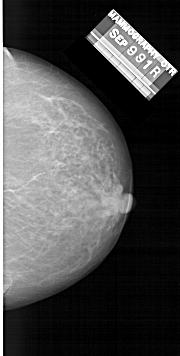

A_1481_1.RIGHT_MLO

RIGHT_CC LINES 6046 PIXELS_PER_LINE 3046 BITS_PER_PIXEL 12 RESOLUTION 43.5 NON_OVERLAY

RIGHT_MLO LINES 6646 PIXELS_PER_LINE 3751 BITS_PER_PIXEL 12 RESOLUTION 43.5 NON_OVERLAY